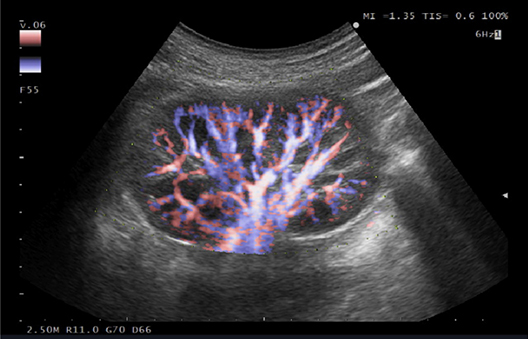

eFLOW es una tecnología de mapeo de flujo que permite una representación precisa y detallada de la dinámica del flujo sanguíneo.

Su excepcional resolución espacial permite una delineación precisa de los vasos sanguíneos finos y más grandes.